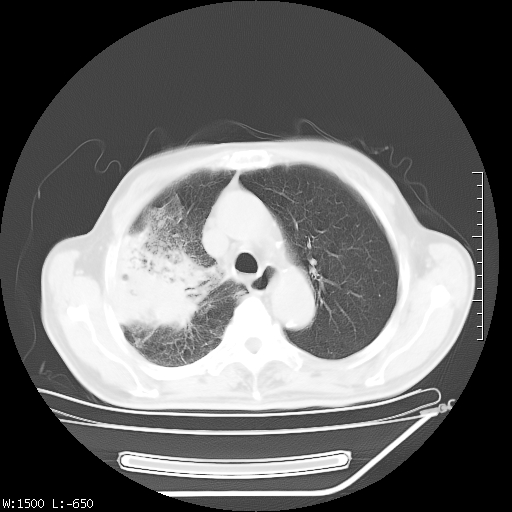

标题: CT23994:男、72、咳嗽、气短两月余,近来消瘦。 [打印本页]

标题: CT23994:男、72、咳嗽、气短两月余,近来消瘦。

tb可能性大(双肺均可见片状密度增高灶,其内可见低密度空洞)。

右上肺大片状密度增高影,与胸膜关系密切,内见低密度透亮影,胸膜下可见三角形不张影,左下肺沿支气管走形结节影,纵膈内淋巴结显示。考虑结核并疤痕性不张可能性大,建议穿刺活检,排除肺泡癌。